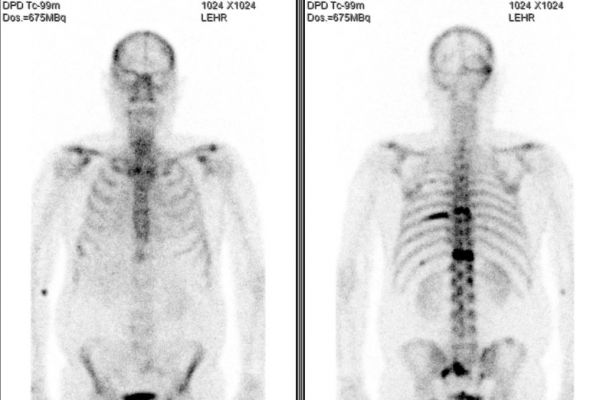

Knochen-/ Skelettszintigrafie: Untersuchung des Knochenstoffwechsels. Hierzu wird eine schwach strahlende Substanz in eine Armvene injiziert und später wird deren Verteilung im Körper gemessen. Nebenwirkungen treten dabei nicht oder sehr selten auf.

Meist werden bereits während oder kurz nach der Injektion erste Aufnahmen angefertigt. Anschließend sollten Sie bis zum Beginn der Aufnahmen nach 2-3 Stunden etwa 1 1/2 l Flüssigkeit, z.B. Wasser, Tee oder Saft trinken. Essen dürfen Sie ohne Einschränkung.

Die eigentliche Aufnahmen werden durchgeführt, nachdem sich die Substanz im Körper verteilt hat. Dies dauert 2-3 Stunden. Während der Aufnahme liegen Sie auf einer Liege und die Gammakamera fährt über Sie hinweg. Eventuell sind anschließend noch Schichtaufnahmen (SPECT-Aufnahmen) notwendig.